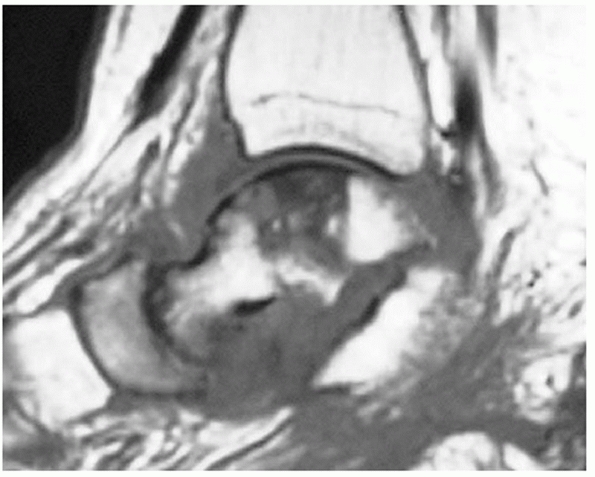

![]() |

|

FIGURE 58-17

This T1-weighted MRI scan was obtained 6 months after a talar fracture-dislocation and demonstrates osteonecrosis of the talar body. The region of osteonecrosis corresponds to the distribution of the artery of the tarsal canal. The scan also demonstrates arthritis of the talonavicular and subtalar joints, subluxation of the subtalar joint, and extensive fluid accumulation around the talus in keeping with a diagnosis of infection. |